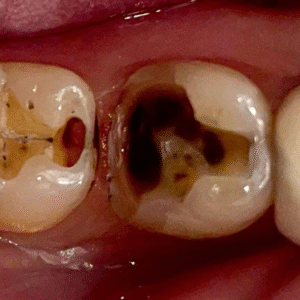

para restaurar dentes

extensamente destruídos

…aqueles tratamentos extensos que tem tudo para dar errado com resina indireta, mas tem remanescente suficiente que contraindica uma coroa de porcelana.

Sentiu que não deveria desgastar remanescente , mas temia que uma resina direta não suportasse o esforço mastigatório?

Mas ninguém te mostra de fato como lidar com casos extensos, cúspides fraturadas ou restaurações amplas sem partir direto para cerâmica ou longos protocolos.